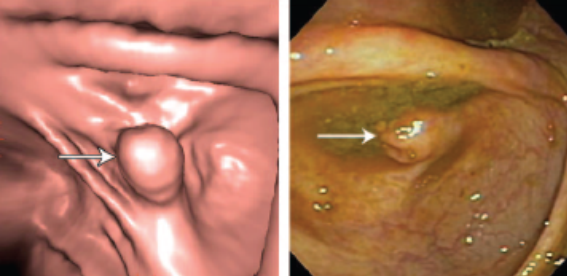

结肠CAD(息肉检测)

结肠息肉指的是隆起于结肠黏膜表面的边界清楚的病灶,根据病变性质及形态特征,为分为腺瘤和息肉两大类。

虚拟结肠镜和光学结肠镜下的息肉